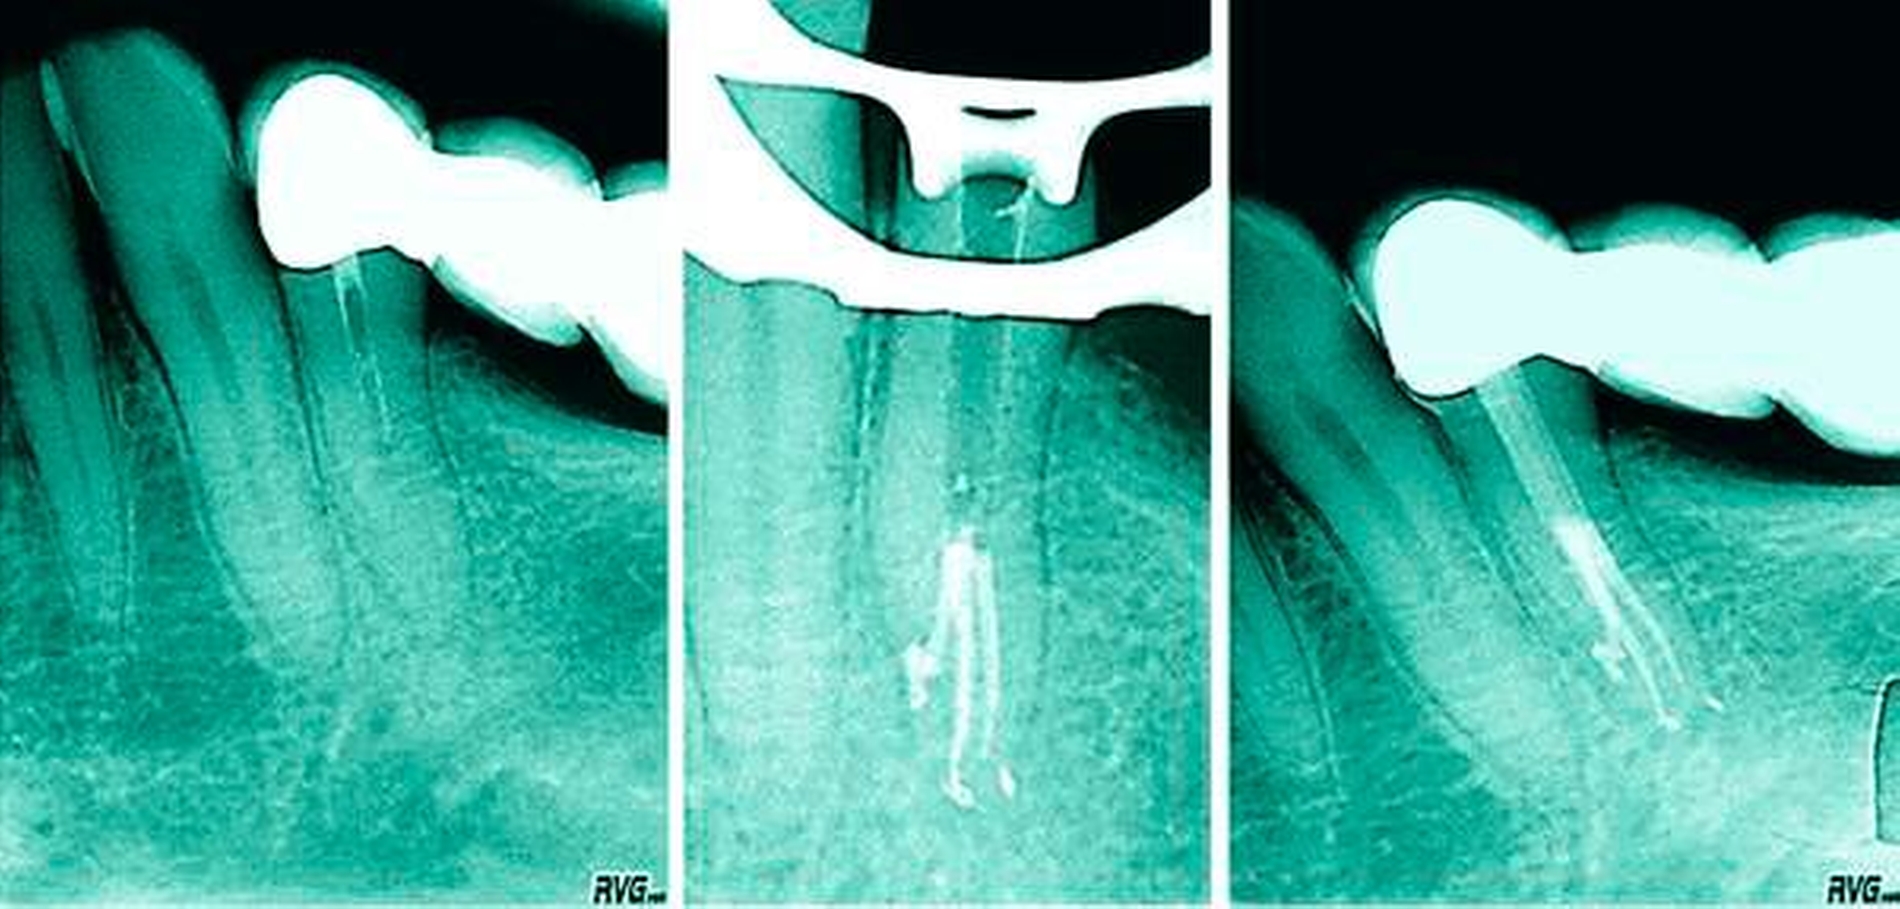

Wie eingangs erwähnt sind die lingualen Kanalabzweigungen im mittleren und im apikalen Drittel nicht durch „Lesen“ des Dentins am Kavumboden zu erkennen. Diese Abzweigung ist nicht selten fast waagerecht und initial meist nur mit vorgebogenen Instrumenten ertastbar (Abbildung 11). Hier bieten sich kleine Stahlinstrumente der Größen 08 und 10 sowie Endodontie-Sonden mit Handgriff an (zum Beispiel Microopener der Firma Dentsply Sirona). Oft lassen sich solche Aufzweigungen erst nach sonoabrasiver Bearbeitung der lingualen Kanalwand finden und können dann gezielt präpariert werden. Der Zugang und die Instrumentierung der lingualen Abzweigung gestalten sich aufgrund der in Abbildung 11 gezeigten Winkel sehr schwierig – man sollte einen sehr guten Zugang zum lingualen Kanalanteil präparieren, um den Apex sicher erreichen zu können.

Klinik bei schwierigen Kanalkonfigurationen